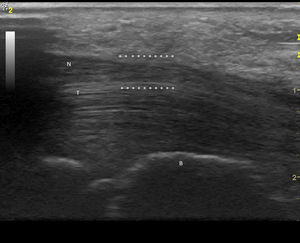

Observación clínicaMujer de 84 años, hipertensa controlada, presentaba desde hace 2 meses lesiones cutáneas en ambas manos de tipo vasculítico asociadas a cianosis del 1.er, 2.° y 3.° dedos, y a dolor intenso que motivaron hospitalización en urgencia por sospecha de vasculitis sistémica. En la anamnesis dirigida, no había elementos de conectivopatía ni consumo de drogas. Recibía enalapril para tratar su hipertensión arterial. En el examen físico destacaban lesiones periungueales, en pulpejos, indicativas de vasculitis, pero llamaba la atención su distribución dermatómica, la severa hipoestesia asociada en el mismo territorio y la importante atrofia de la eminencia tenar, de manera bilateral (fig. 1). El resto del examen era normal; en particular, no había lesiones cutáneas en otras localizaciones y su tensión arterial era normal. Se realizó estudio: hemograma y velocidad eritrocitaria de sedimentación normales, función renal y orina completa normales, factor reumatoideo negativo, anticuerpos antinucleares negativos, perfil ENA detallado negativo, ANCA c y p negativos. La paciente refería de alteraciones de la sensibilidad con parestesias nocturnas y falta de fuerza en manos con tiempo de evolución prolongado, por lo que ya había consultado. Se había hecho el diagnóstico de STC, realizándose una electromiografía de extremidades superiores un año antes. Esta mostraba ya un severo atrapamiento de ambos nervios medianos a nivel de los túneles carpianos, con denervación completa de las eminencias tenares. Se realizó estudio ultrasonográfico de la paciente evidenciando a la entrada del túnel a nivel del pisiforme, un nervio mediano derecho de 17mm2 de área (normal=± 10mm2)1,2 (fig. 2), con presencia central de una arteria mediana remanente (fig. 3). El nervio mediano izquierdo estaba también engrosado, con un área nivel del pisiforme de 18mm2. Ambos nervios aparecían atrapados en el túnel carpiano en los cortes longitudinales (fig. 4).

Corte transversal del nervio mediano derecho a nivel de la entrada del túnel del carpo, con medición del área del nervio con elipse (0,17cm2), a nivel del pisiforme P (B: hueso grande). (Imagen obtenida con ecógrafo General Electrics LOGIC e, con un transductor linear de 8-12 mHz usando para esta imagen una frecuencia de 12 mHz y un agrandamiento máximo).